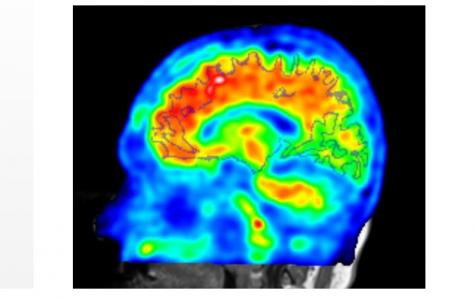

De quoi s’agit-il ? D’une échelle, développée à l’université, la Loewenstein-Acevedo Scales for Semantic Interference and Learning ou LASSI-L. L’auteur principal, le Dr David Loewenstein, directeur du Centre pour la neuroscience cognitive et professeur de psychiatrie explique que cette échelle a permis d’identifier des déficits de mémoire spécifiques chez les participants de l’étude, qui s'alignent sur les résultats de l'imagerie par scintigraphie cérébrale (voir visuel) montrant une accumulation anormale d'amyloïde dans le cerveau.

Ici, les chercheurs apportent les premiers résultats d’efficacité de ce test relativement simple puisqu’il repose sur 2 listes de 5 mots. Selon cette étude, l’échelle permettrait en effet de détecter les premiers changements cognitifs annonçant la maladie d'Alzheimer. En effet, les patients positifs à l'imagerie « bêta-amyloïde » étaient également ceux commettant un nombre significativement plus élevé d'erreurs d'intrusion sémantique. Ainsi, l'association du test LASSI-L à l’examen par imagerie semble très prometteur dans l'évaluation clinique de la maladie d'Alzheimer préclinique.